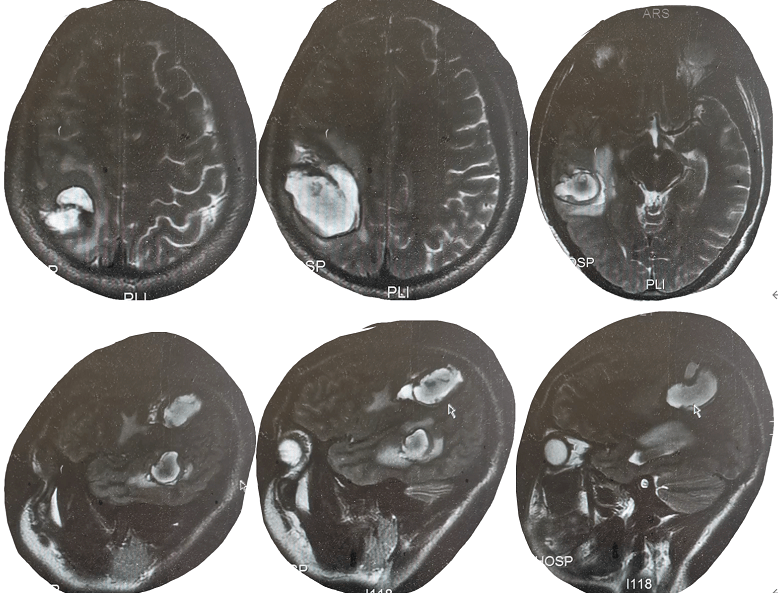

【病例讨论】大家看看,这是脑肺吸虫病吗?

图片尺寸640x480